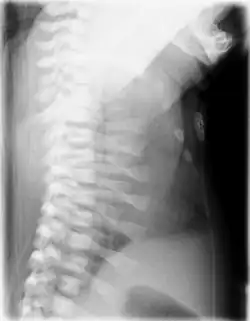

CXR of a newborn with asphyxiating thoracic dysplasia. Note the short ribs.

Lateral CXR of the same person above

Jeune syndrome is a rare genetic disorder that affects the way a child's cartilage and bones develop. It begins before the child is born and primarily affects the child's rib cage, pelvis, arms and legs.[5] Usually, problems with the rib cage cause the most serious health problems for children with Jeune syndrome. Their rib cages (thorax) are smaller and narrower than usual, which inhibits the child's lungs from developing fully or expanding when they inhale. The child may breathe rapidly and shallowly. They may have trouble breathing when they have an upper or lower respiratory infection, like pneumonia. Breathing trouble can range from mild to severe. In some children, it is not noticeable, aside from fast breathing; however, in others, breathing problems can be fatal. About 60% to 70% of children with this condition die from respiratory failure as babies or young children. Children with Jeune syndrome who survive often develop problems with their kidneys, and over time they may experience kidney failure.[2] As a result, few children with Jeune syndrome live into their teen years. Children with Jeune syndrome have a form of dwarfism. They are short in stature, and their arms and legs are shorter than most people's.[6]